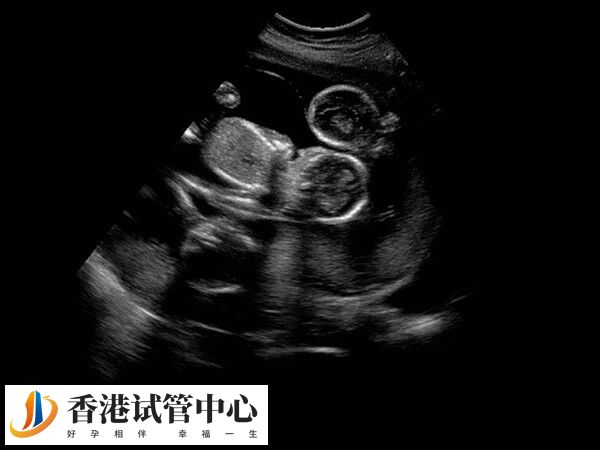

在试管治疗中,患者如果移植的是质量不好的胚胎,那么可能导致胎停的时间多发生在12周左右。这是因为这一时间段是关键的孕早期,胚胎在此阶段对营养和激素的需求极高,任何不足或异常都可能导致胎停。不过因个体差异较大,不过患者也可能在孕1-3周出现胎停,具体以实际为准。

一般来说,由于胚胎质量不好引起的胎停基本是出现在孕初期,这段时期属于胎儿的成形期,如果胚胎质量不好,在这个阶段就会胎停或者流产。大概时间在怀孕12周前就会胎停。所以在孕12周前孕妇要警惕胎停的情况出现,出现胎停情况要立即就医,尽快终止妊娠,否则就容易导致稽留流产,引起大出血的情况。